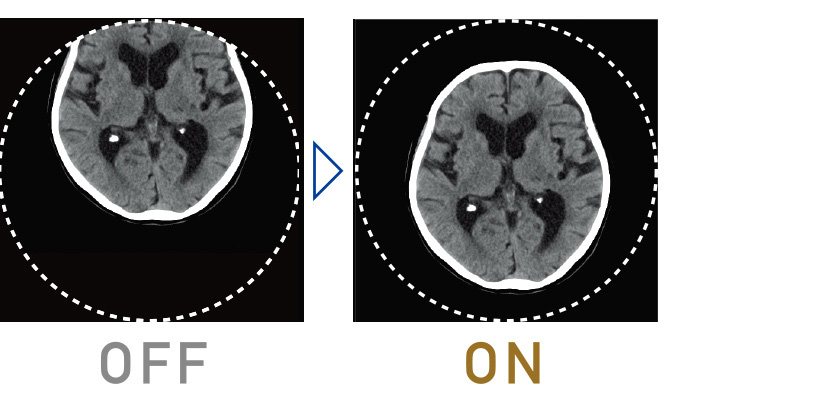

İteratif İşleme, dozun azaltılmasında kullanılır ancak çok fazla hesaplama gerektirir, bu da rutin incelemelerde uygulanmasını zorlaştırır. Supria 128’de, görüntü işleme birimi yenilenip işleme hızı iyileştirilmiştir, böylece rutin incelemelerde İteratif İşleme (Intelli IP) kullanımı kolaylaşmıştır.

Her tesis için optimum ayarlar

Gürültü azaltma gücü, 7 farklı seviyede seçilebilir. Tesisin işletme politikasına göre uygun bir doz ile görüntü gürültüsünü ve artefaktları azaltarak üstün kaliteli görüntüler sağlıyoruz.